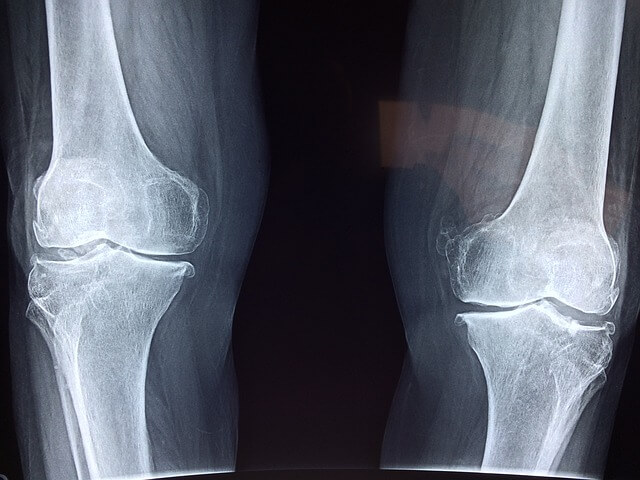

손가락 관절염은 퇴행성인지 류마티스인지에 따라 다양한 방식으로 나타날 수 있습니다.

각 유형의 증상을 이해하는 것은 조기 진단과 효과적인 치료에 중요합니다.

퇴행성 관절염 증상

• 통증 : 통증은 주로 관절에 발생하며 일반적으로 손을 사용한 후 악화됩니다.

• 부기 : 손가락 관절이 부어오르고 만졌을 때 뜨거울 수 있습니다.

• 경직 : 손가락이 경직되어 특히 아침에 움직임이 어려워집니다.

• 변형 : 시간이 지남에 따라 손가락 관절이 두꺼워지거나 변형될 수 있습니다.

• 저림 : 손가락이 저리거나 차가워질 수 있습니다.

손가락 관절염의 주요 원인은 크게 퇴행성 관절염과 류마티스 관절염 두 가지로 나눌 수 있습니다. 효과적인 치료와 관리를 위해서는 각 유형의 근본 원인을 이해하는 것이 필수적입니다.

퇴행성 관절염의 원인

1. 노화

나이가 들수록 관절을 보호하는 연골이 점차 닳아 손상됩니다. 이러한 자연적인 마모는 손가락 관절염의 가장 흔한 원인입니다.